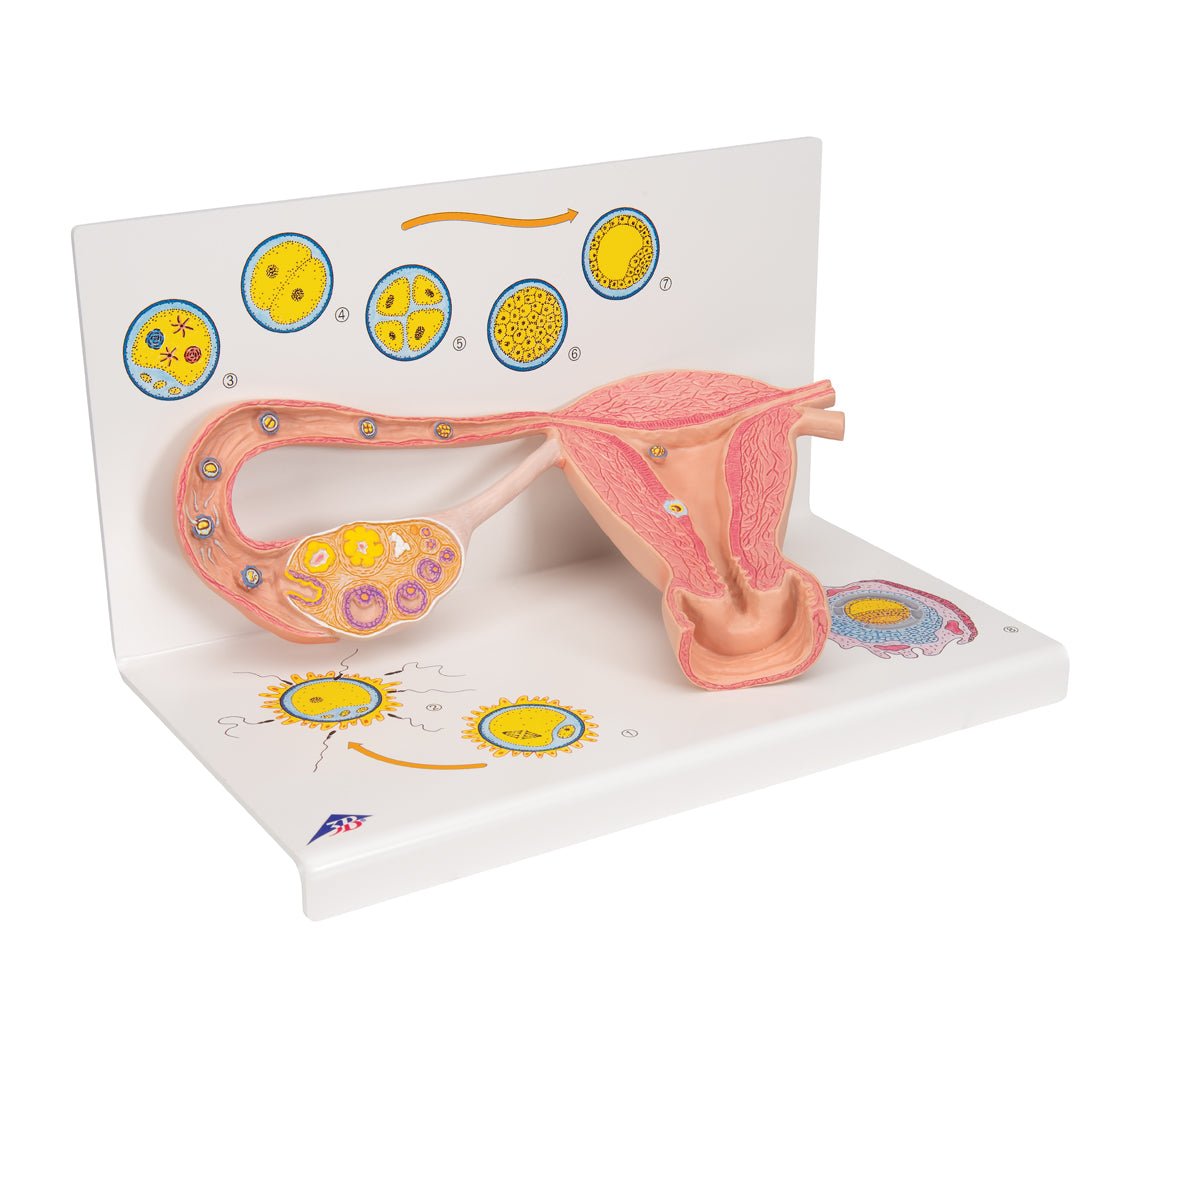

Salg af anatomiske modeller er det bærende element i eAnatomi, selvom vi også bruger mange ressourcer på at udvikle vores egne anatomiske materialer som fx plakater. Anatomiske modeller anvendes til forskellige formål og kan både vise afgrænset væv, organer samt organsystemer. Søger du en simpel model af knoglevæv eller måske en avanceret torso-model baseret på MRI teknologi, kan du finde det hele på eanatomi.com.